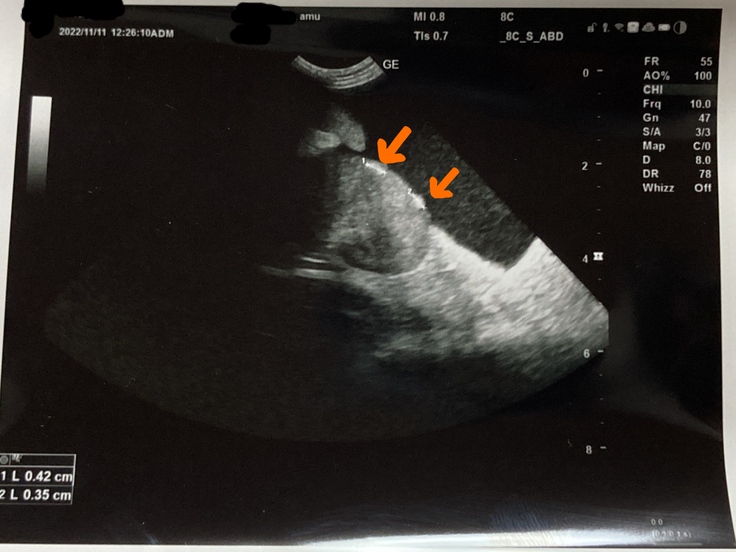

11/11投薬開始して2週間、大分、腹水減り、エコー検査で、腎臓に結節がみつかりました。

セカンドの病院に通っていたら、わからなかったかもしれません。

ウェットタイプ→混合タイプだとわかりました。

混合タイプは投薬量を慎重にする必要があるそうです。